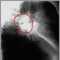

Metastatic cancer to the lung is cancer that starts somewhere else in the body and spreads to the lungs.

Metastatic tumors in the lungs are cancers that developed at other sites and spread through the bloodstream or lymphatic system to the lungs. Common tumors that spread to the lungs include:

In most cases, metastatic cancer to the lung is a sign that the cancer has spread into the bloodstream. Usually cancer will be present even in places not seen by CT scans. In these circumstances, removing the visible tumors with surgery is usually not beneficial. Chemotherapy is usually the treatment of choice.

Sometimes when the primary tumor has been removed and the cancer has spread to only limited areas of the lung, the lung tumors can be removed with surgery. However, the main tumor must be curable, the lung tumors must be able to be completely cut out, and the patient must be strong enough to go through the surgery and recovery.